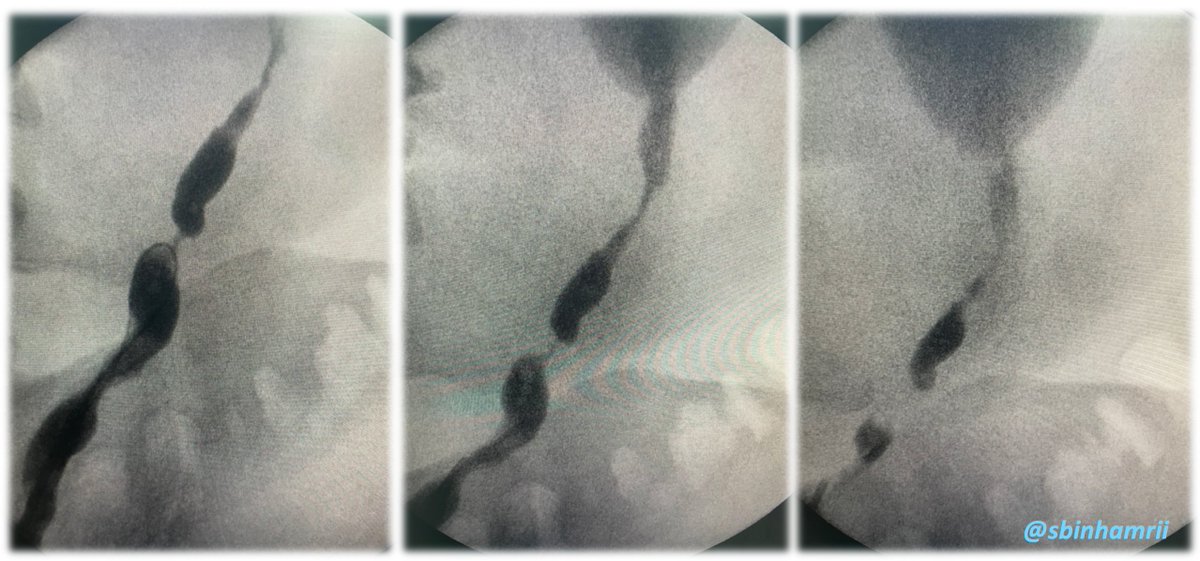

🔴 #Laser is my choice in impacted Stone

🔴 Remember Laser is Light ... Light is Heat

🔴 Use Very Low Power to minimize the Ureteric wall insult

🔴 Do only the Center & Fragments will fall into You with Venturi Effect

⚪ Do it with Passion

@PETRAurogroup @PEARLSendouro

🔴Ureteric Stone with Sever Impaction

🔴No passable GW

🔴TFL (Centre) away from Mucosa with Minimal retropulsion 20 Hertz - 0.3 J

🔴Bleeding impacted site is a good sign

👉 How long you would Leave a stent ?

#Endourology @Urosome @PETRAurogroup

@sbinhamrii @PETRAurogroup @PEARLSendouro I agree with this. Also, I feel it is important to move the stone/fragments away from the point of inflammation to complete the laser lithotripsy. And I use tandem stents